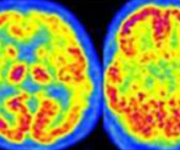

Durante un episodio anginoso, l’ECG può mostrare una depressione del tratto ST, segno di ischemia miocardica. Questa alterazione è solitamente transitoria e scompare con la risoluzione dei sintomi. Nei periodi tra un episodio e l’altro, invece, l’ECG può risultare normale nel 50% dei casi, mentre in altri pazienti si osservano alterazioni aspecifiche delle onde T o del tratto ST.

I test da sforzo e provocazione dell’ischemia servono a riprodurre i sintomi anginosi in un contesto controllato, monitorando contemporaneamente l’ECG. Un sottoslivellamento del tratto ST durante l’esercizio fisico è un forte indicatore di ischemia miocardica.